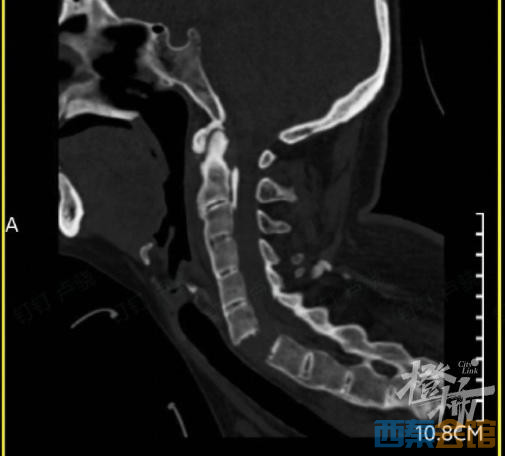

当时,刘女士出现颈部疼痛、四肢无力的症状,紧接着发现自己全身不能活动。随后,她被紧急送往附近的医院救治,通过颈椎影像检查后发现,刘女士颈椎6-7节完全断离,颈椎骨折造成脊髓损伤,导致全身瘫痪。

△检查发现,刘女士的颈椎完全断离。图源:橙柿互动

刘女士转到浙大二院做了手术,浙二骨科脊柱外科张宁主任医师介绍,刘女士本身有强直性脊柱炎的基础疾病,这是一种累及脊柱为主的慢性炎症性疾病,主要表现为脊椎及腰背部疼痛及僵硬。